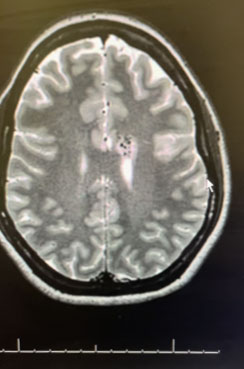

Head CT was consistent with a small acute left intraventricular hemorrhage (Figure 1).

Fig. 1